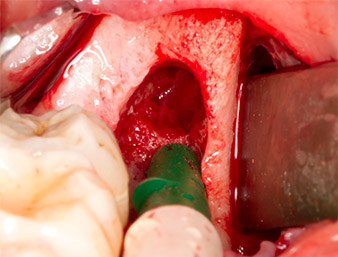

Sous bloc nerveux et anesthésie locale, le site d’intervention est ouvert et les tissus mous sont exposés afin d’accéder à la zone rétromolaire buccale (Fig. 3).

Le tissu recouvrant le reste radiculaire n’est pas entièrement ossifié et est essentiellement constitué de tissu de granulation modifié par l'inflammation (Fig. 4).

Pour obtenir un matériau autogène en vue du traitement ultérieur de la plaie, des fragments osseux sains sont collectés autour du reste radiculaire à l'aide d’un insert piézochirurgical (Piezomed B5) (Fig. 5).